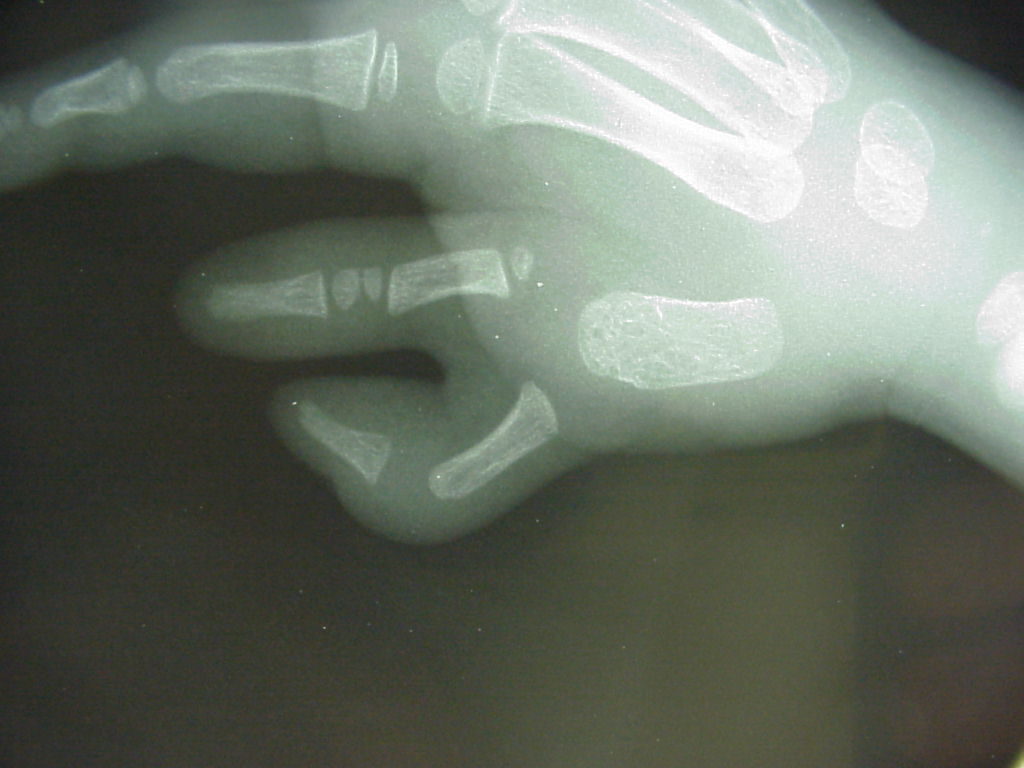

Clinical Example: Polydactyly

polydactyly